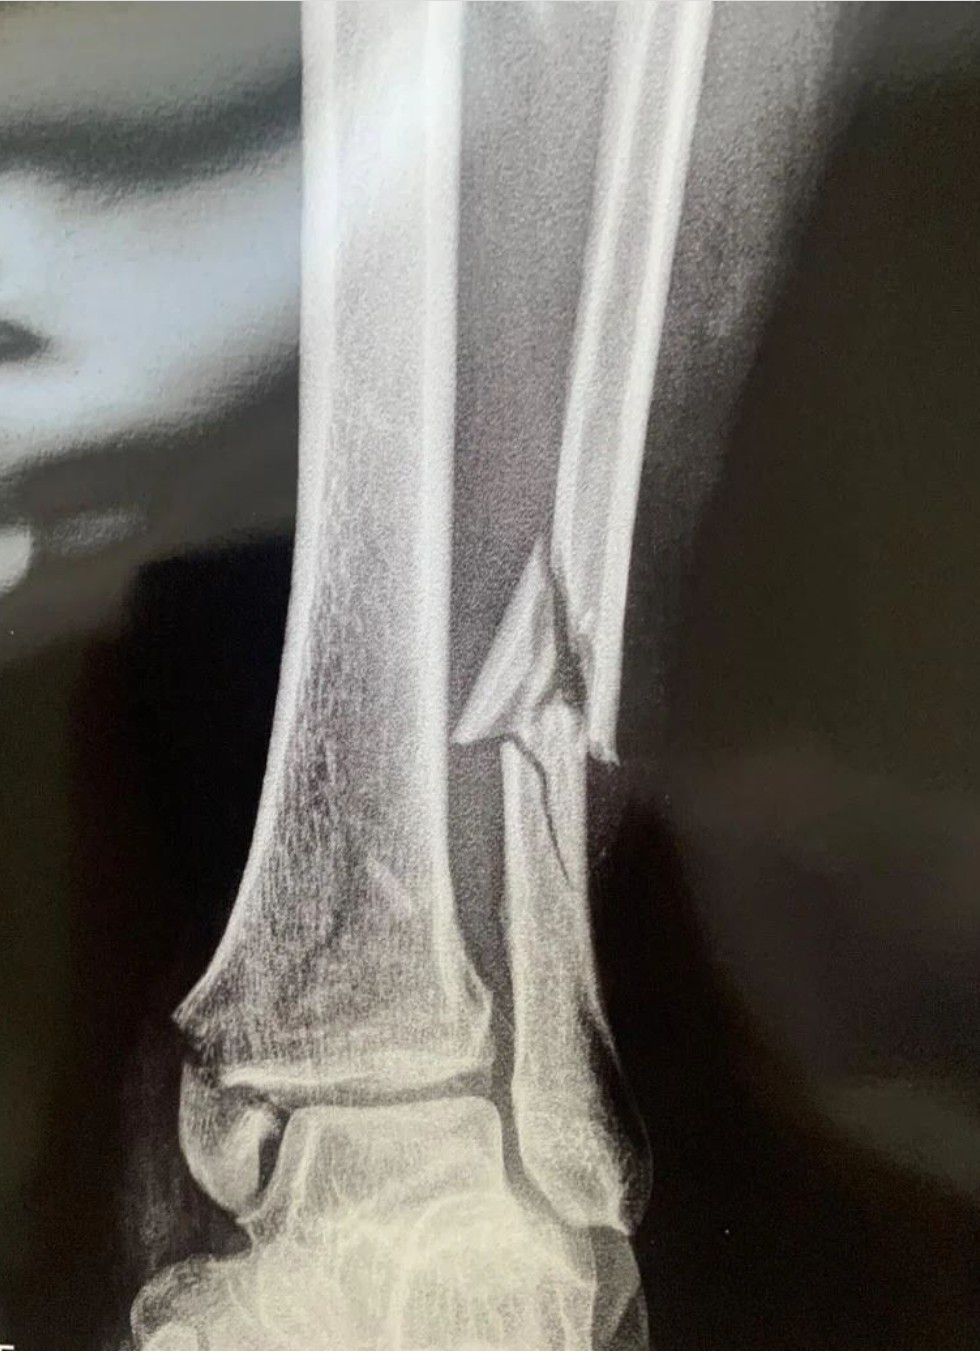

Identify the Bone

Identify the fractured bone.

Tibia and fibula